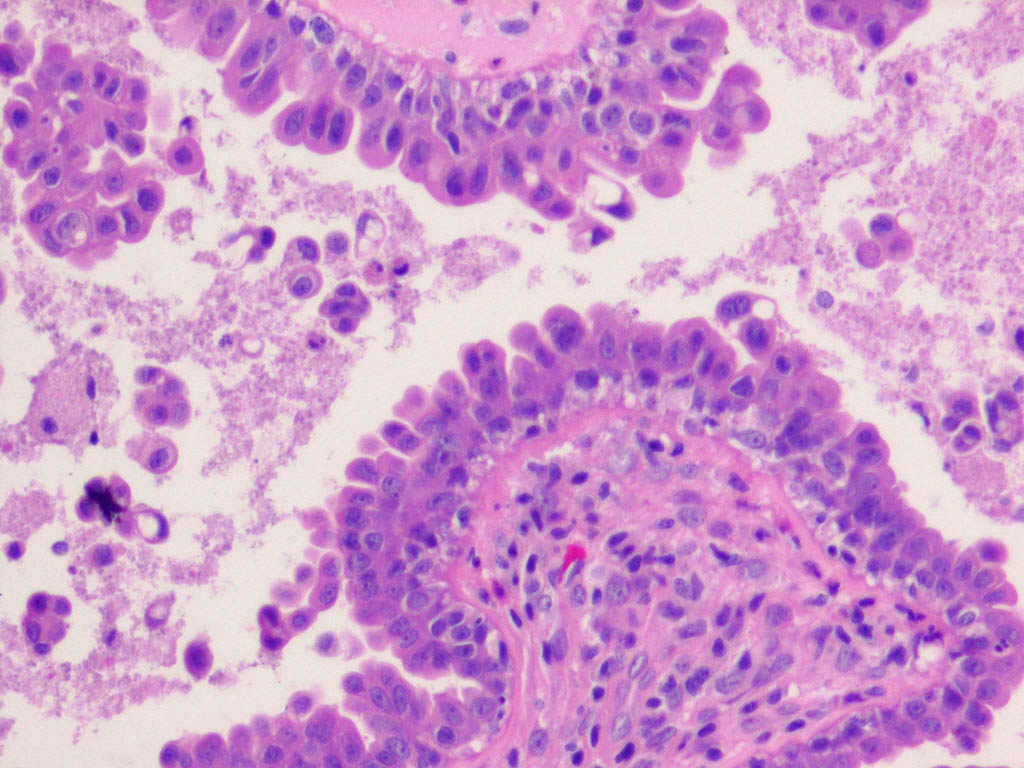

The cyst wall is lined by apocrine-type secretory epithelium. The innermost layer of the wall is composed of a single (occasionally double) layer of cuboidal-to columnar-shaped cells. The nuclei of these cells are positioned basally. The outer layer of cells composing the cyst wall is formed by myoepithelial cells in which the long axes run parallel to the cyst wall.

Well-organized fibrous tissue surrounds the cyst. Papillary projections extend from the secretory layer into the cyst cavity, depicting decapitation secretion. The secretory cells contain periodic acid-Schiff–positive, diastase-resistant granules and occasionally contain pigment granules, which provide the brown color of the cystic fluid. This pigment is neither melanin nor hemosiderin. On electron microscopy, secretory cells have numerous, dense, lysosomal-type secretory granules typical of apocrine gland cells. They also have an increased number of annulate lamellae, which are unusual in normal apocrine cells.